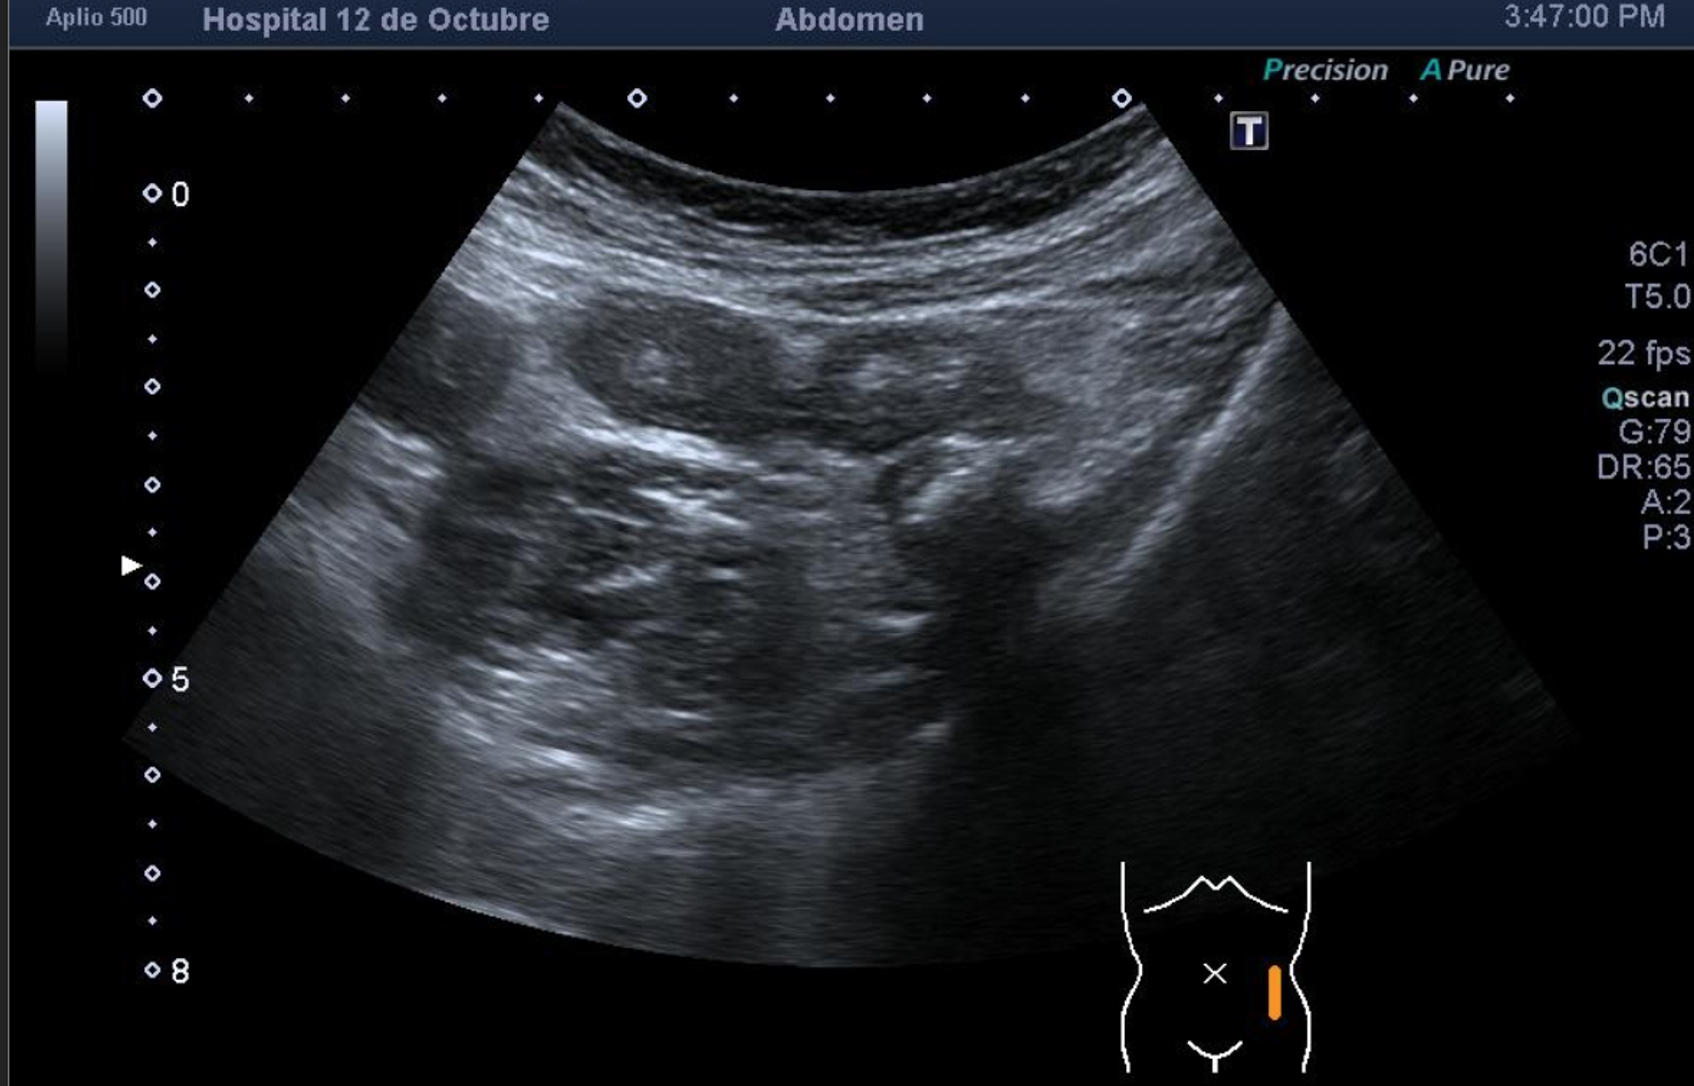

Hallazgos ecográficos

Se explora FII-hipogastrio y en el punto de más dolor se observa engrosamiento de asas de intestino grueso sin peristaltismo y con signos de edema de la grasa adyacente. No líquido libre.

También se realiza ecografia en urgencias del hospital.

En el hospital se realiza una nueva ecografía en el servicio de radiología confirmando el diagnóstico de sospecha: diverticulitis aguda en sigma distal sin datos de complicación. Hinchey 1A.